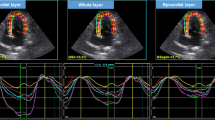

The correlation analysis of data of all cats demonstrated a highly positive correlation between PALS and LA-EF (r = 0.797, P < 0.001) as well as PALS and FAC (r = 0.746, P < 0.001). The peak atrial longitudinal strain moderately correlated with LA-FS (0.538, P = 0.001) (Fig. 2).

Correlations between PALS and other LA function parameters and LA diameter using Pearson’s correlation coefficient; a. PALS and LA-FS (r=0.538, P=0.001) b. PALS and LA-EF (r=0.797, P <0.001) c. PALS and FAC (r=0.746, P <0.001) d. PALS and LAD (r=-0.248, P =0.139) in the control (white) and hypertrophic cardiomyopathy groups (blue). PALS= peak atrial longitudinal strain; LA-FS= left atrial fractional shortening LA-EF= left atrial ejection fraction; FAC =left atrial fractional area change; LAD= left atrial diameter